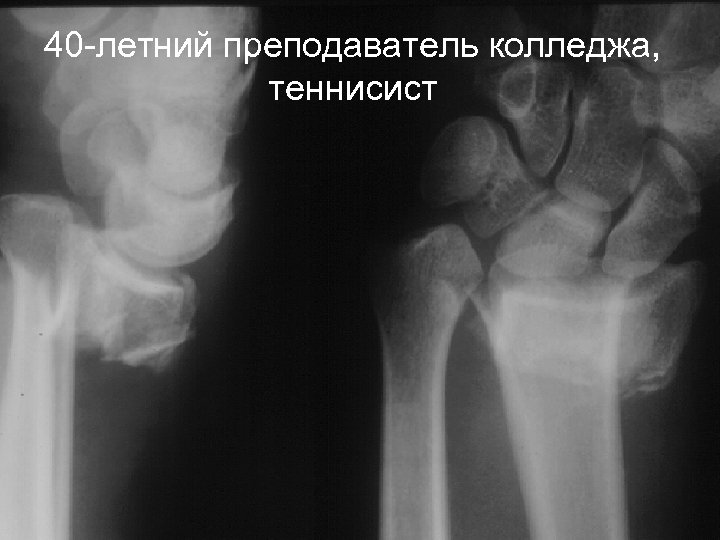

40 -летний преподаватель колледжа, теннисист

Метод лечения - закрытая репозиция, фиксация спицами

Требуется иммобилизация в течение 6 недель Окно в местах проведения спиц